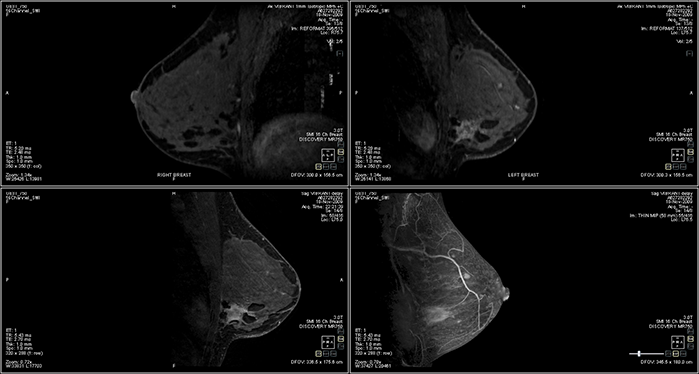

Product Brochure and MRI Sample Image

MRI Image Produced by this System